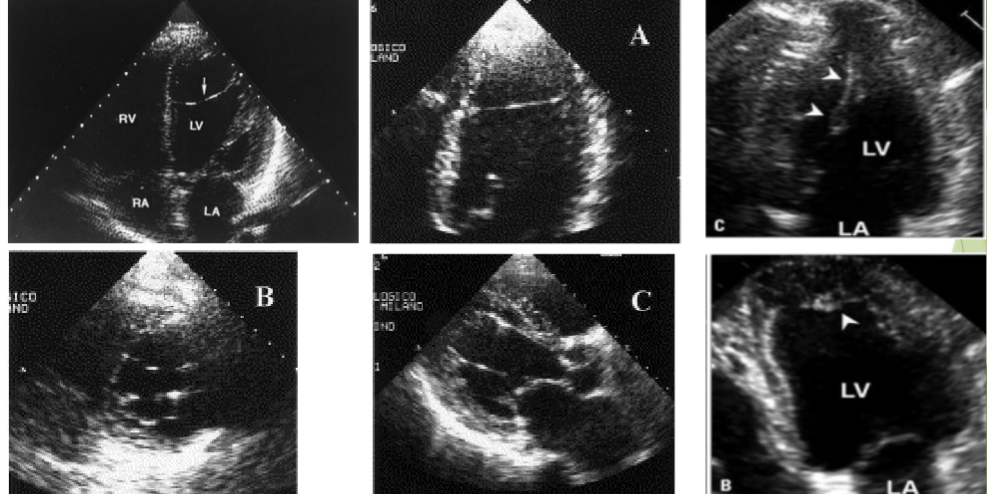

<p>Which of the following window is Apical Window?</p>

Which of the following window is Apical Window?